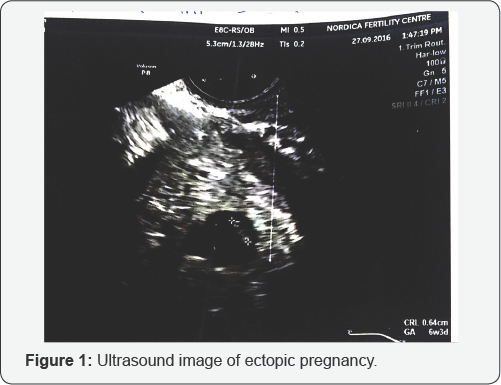

Serial quantitative BHCG was ordered. The first result was 9709Miu/ml and a repeat 48 hours later was 12,102.Miu/ml. a subsequent (3HCG was 15,549.0Miu/ml. The figures were increasing but not doubling. Spotting par vaginam persisted on and off and a repeat scan showed a left adnexial mass consistent with a gestational sac but with non active fetal pole seen. fetal pole with a CRL of 0.64cm, equivalent to 6 weeks and 3 days gestation (Figure 1). A diagnosis of suspected ectopic gestation was made and she was referred for an emergency surgery at the Lagos University Teaching Hospital where history, laboratory tests (positive serum pregnancy test) and ultrasound findings (left adnexal gestational sac with fetal pole, minimal fluid in pouch of Douglas and empty uterus) further confirmed an ectopic pregnancy.